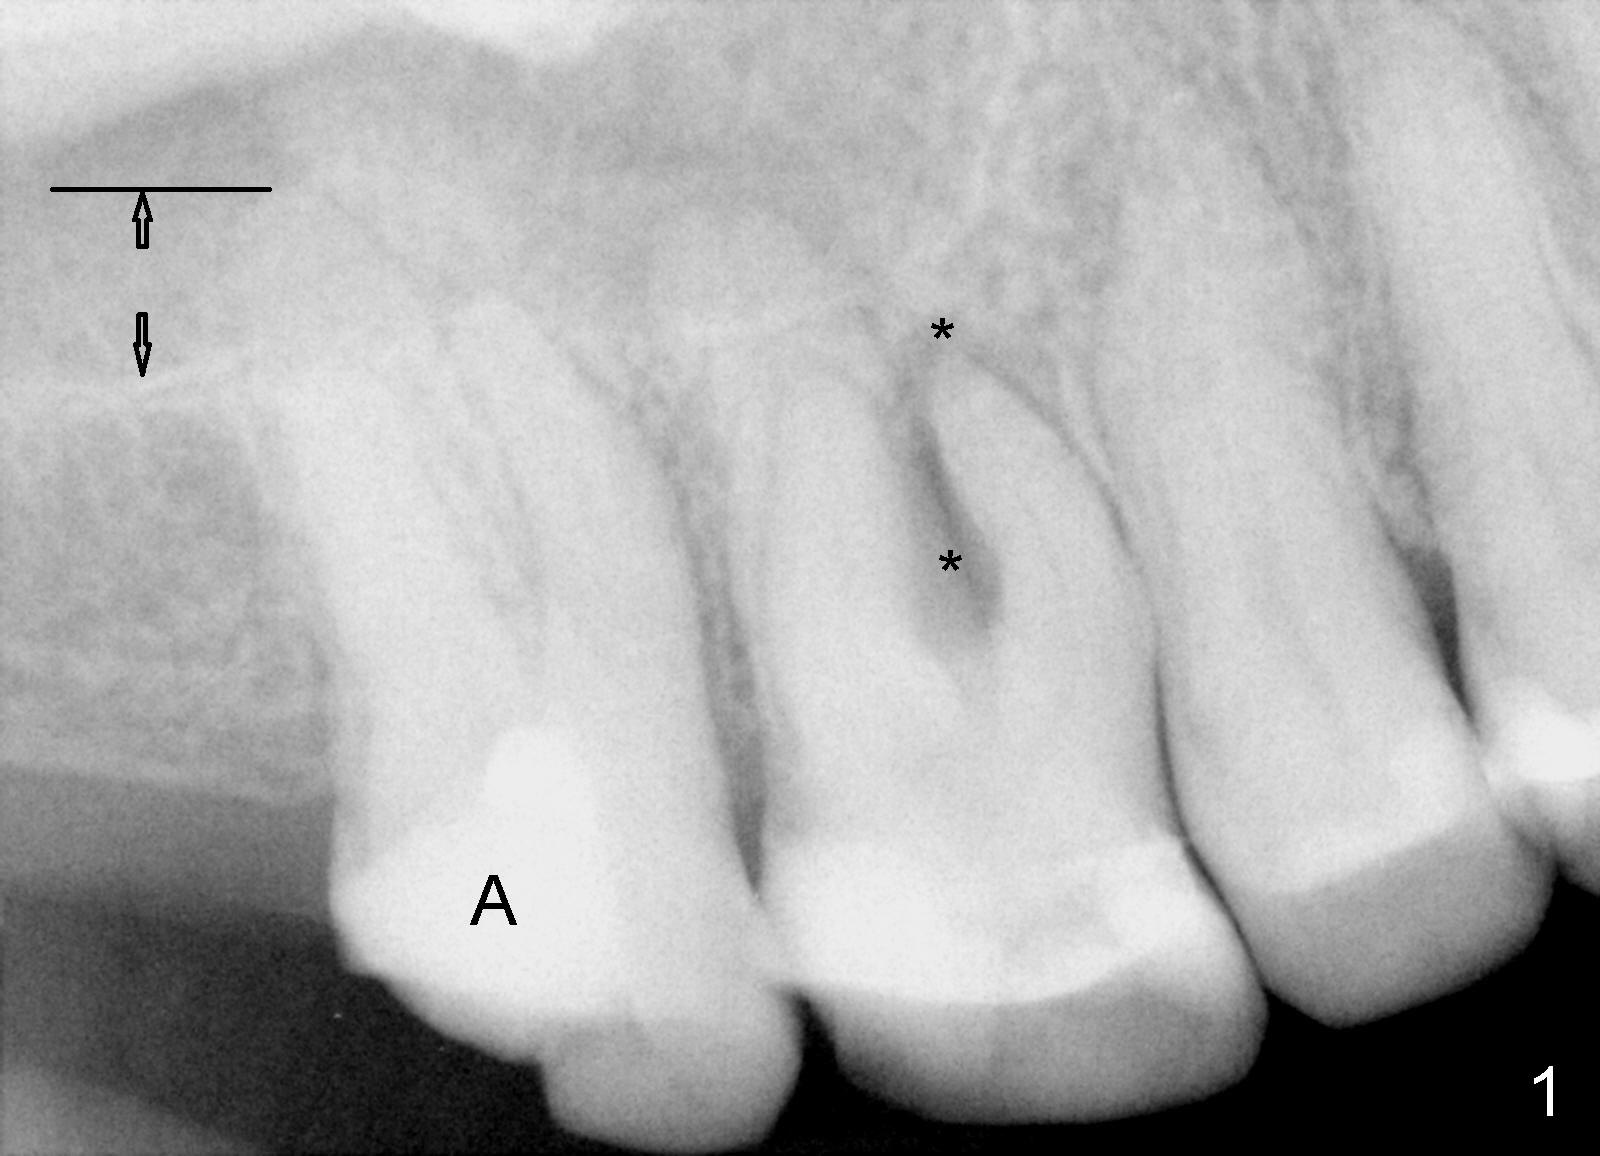

A 51-year-old lady has multiple restorations (Fig.1-3), e.g., amalgam (A in Fig.1) of the upper right 2nd molar as well as history of pulpotomy. The 1st molar has periapical radiolucency (* in Fig.1) and needs root canal therapy. The lower 3rd molar occludes (Fig.2 arrow) with the upper 2nd molar. The latter fractures subgingivally (Fig.3 <) and is extracted with a large MB root (Fig.4) and MB socket (Fig.5). The gingival one third of the palatal wall is defective, as indirectly indicated by granulation tissue palatally (Fig.5 <). So the osteotomy for the immediate implant will not be placed in the palatal socket. The septum is pointed coronally. The pointed portion of the septum is removed; initial osteotomy is formed by 1.5 mm pilot drill in the septum, followed by 2-5 mm osteotomes with the depth of 17 mm. The enlarging osteotomy is deviating buccally; drills are being used to move the osteoomy palatally without much success. When a 5 mm tap is inserted, it is stable and appears to be inside the maxillary sinus (Fig.6). In fact the osteotomy has bony walls around (Fig.7 <), including apical, when the tap is removed. Preop PA shows that the palatal root is apical to the sinus floor (Fig.1 between arrows).